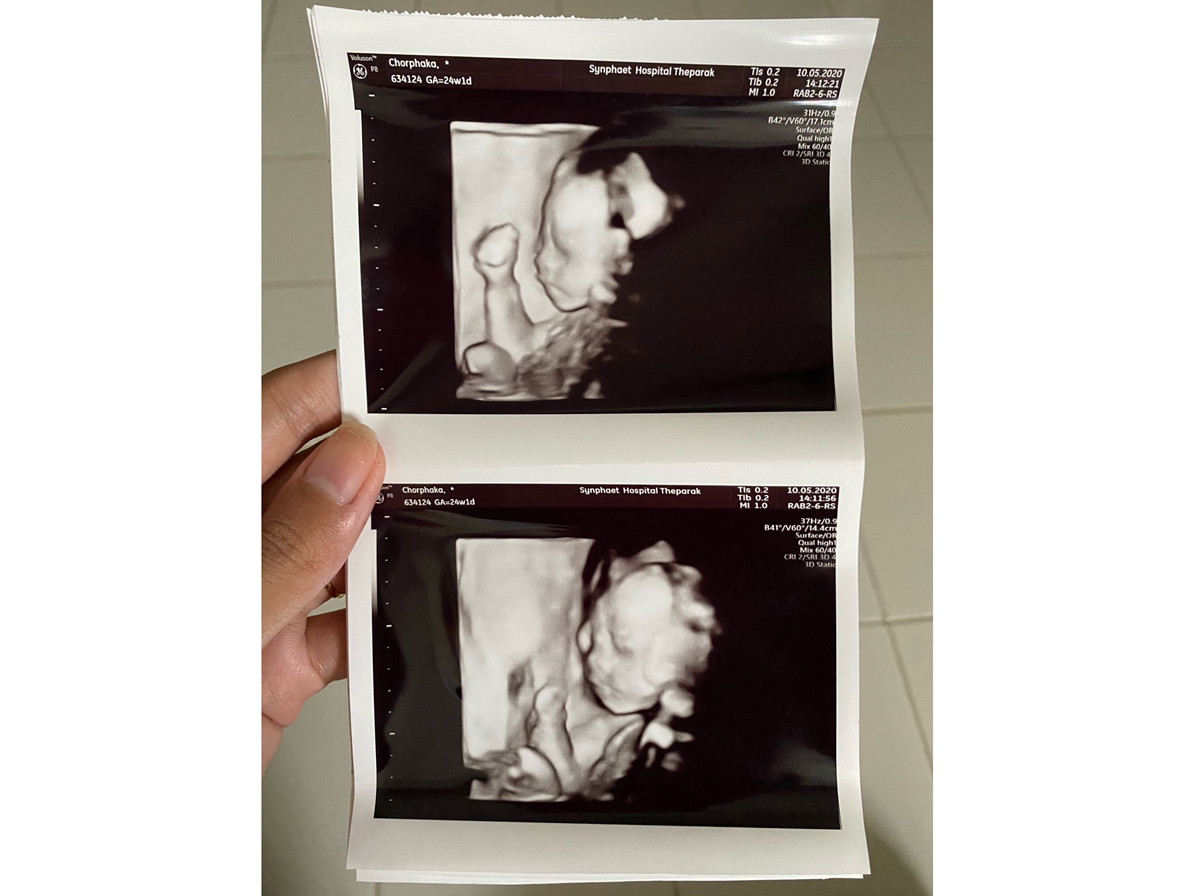

23w ค่ะ